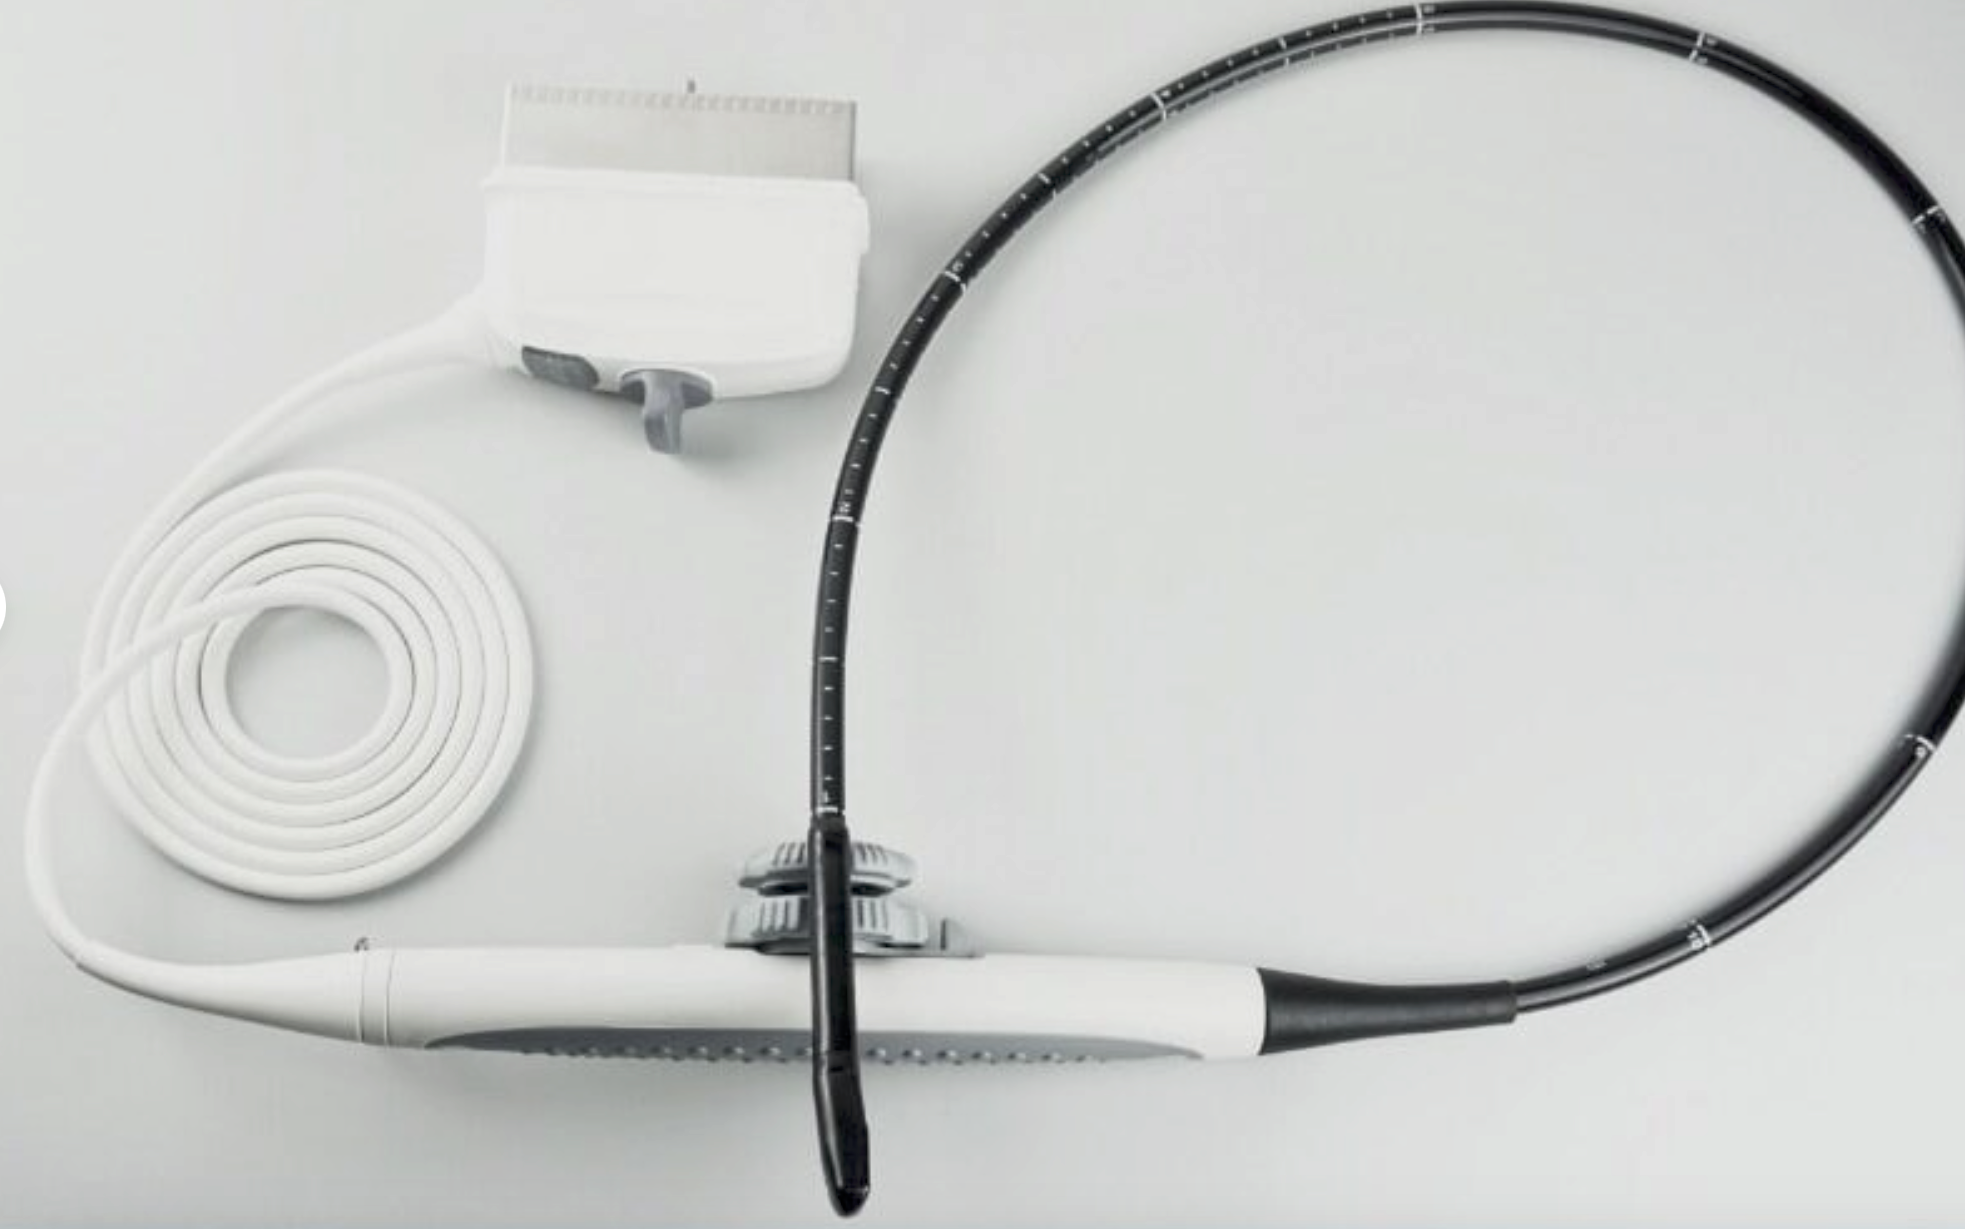

Probe 2: 7.5MHZ Transvaginal probe:gynecologic examination